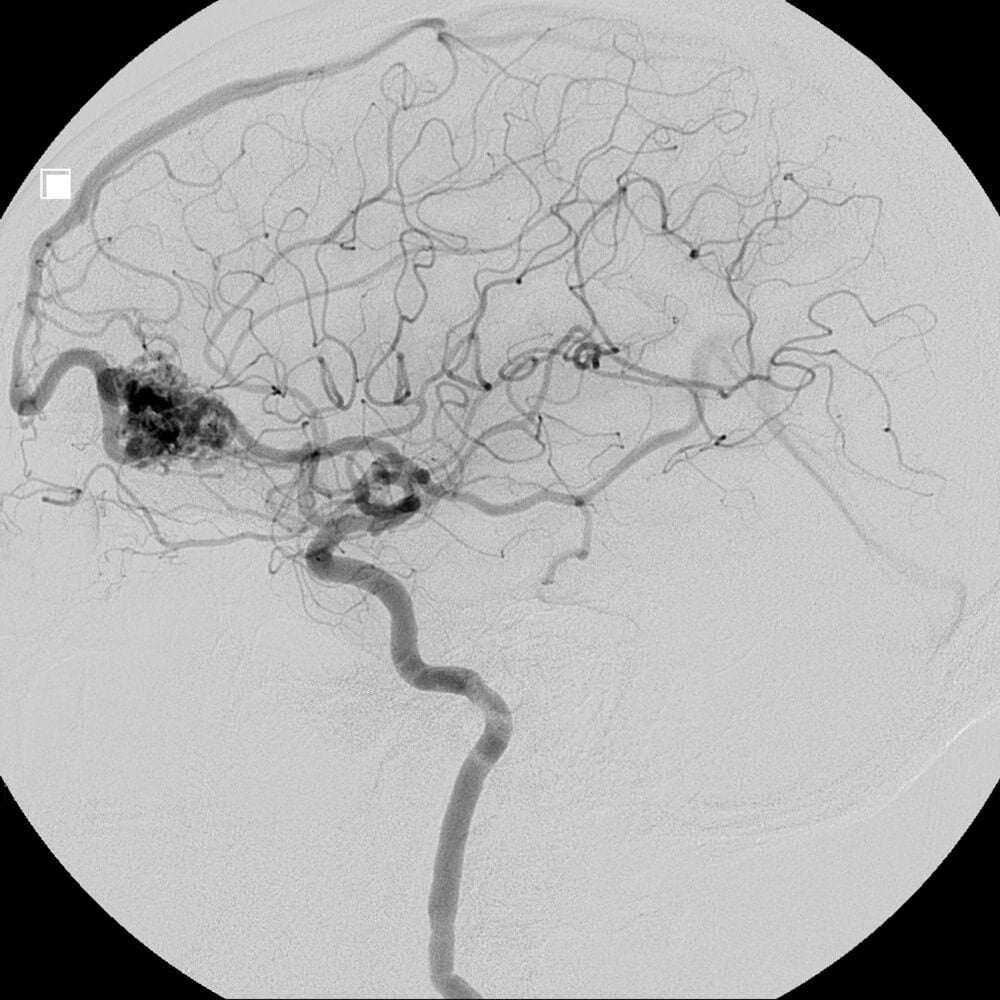

Arteriovenous malformation

There are four main types of vascular malformations: Arteriovenous malformation (AVM), Dural arteriovenous fistula (dAVF), Venolymphatic malformation, and Cerebral cavernous malformation (CCM). Vascular malformations vary significantly on their potential for damage, depending on their type and location. Some may simply be a cosmetic issue; others can be a nuisance, causing a pulsating noise called pulsatile tinnitus, while others pose a risk for brain hemorrhage, strokes, loss of vision, and death.